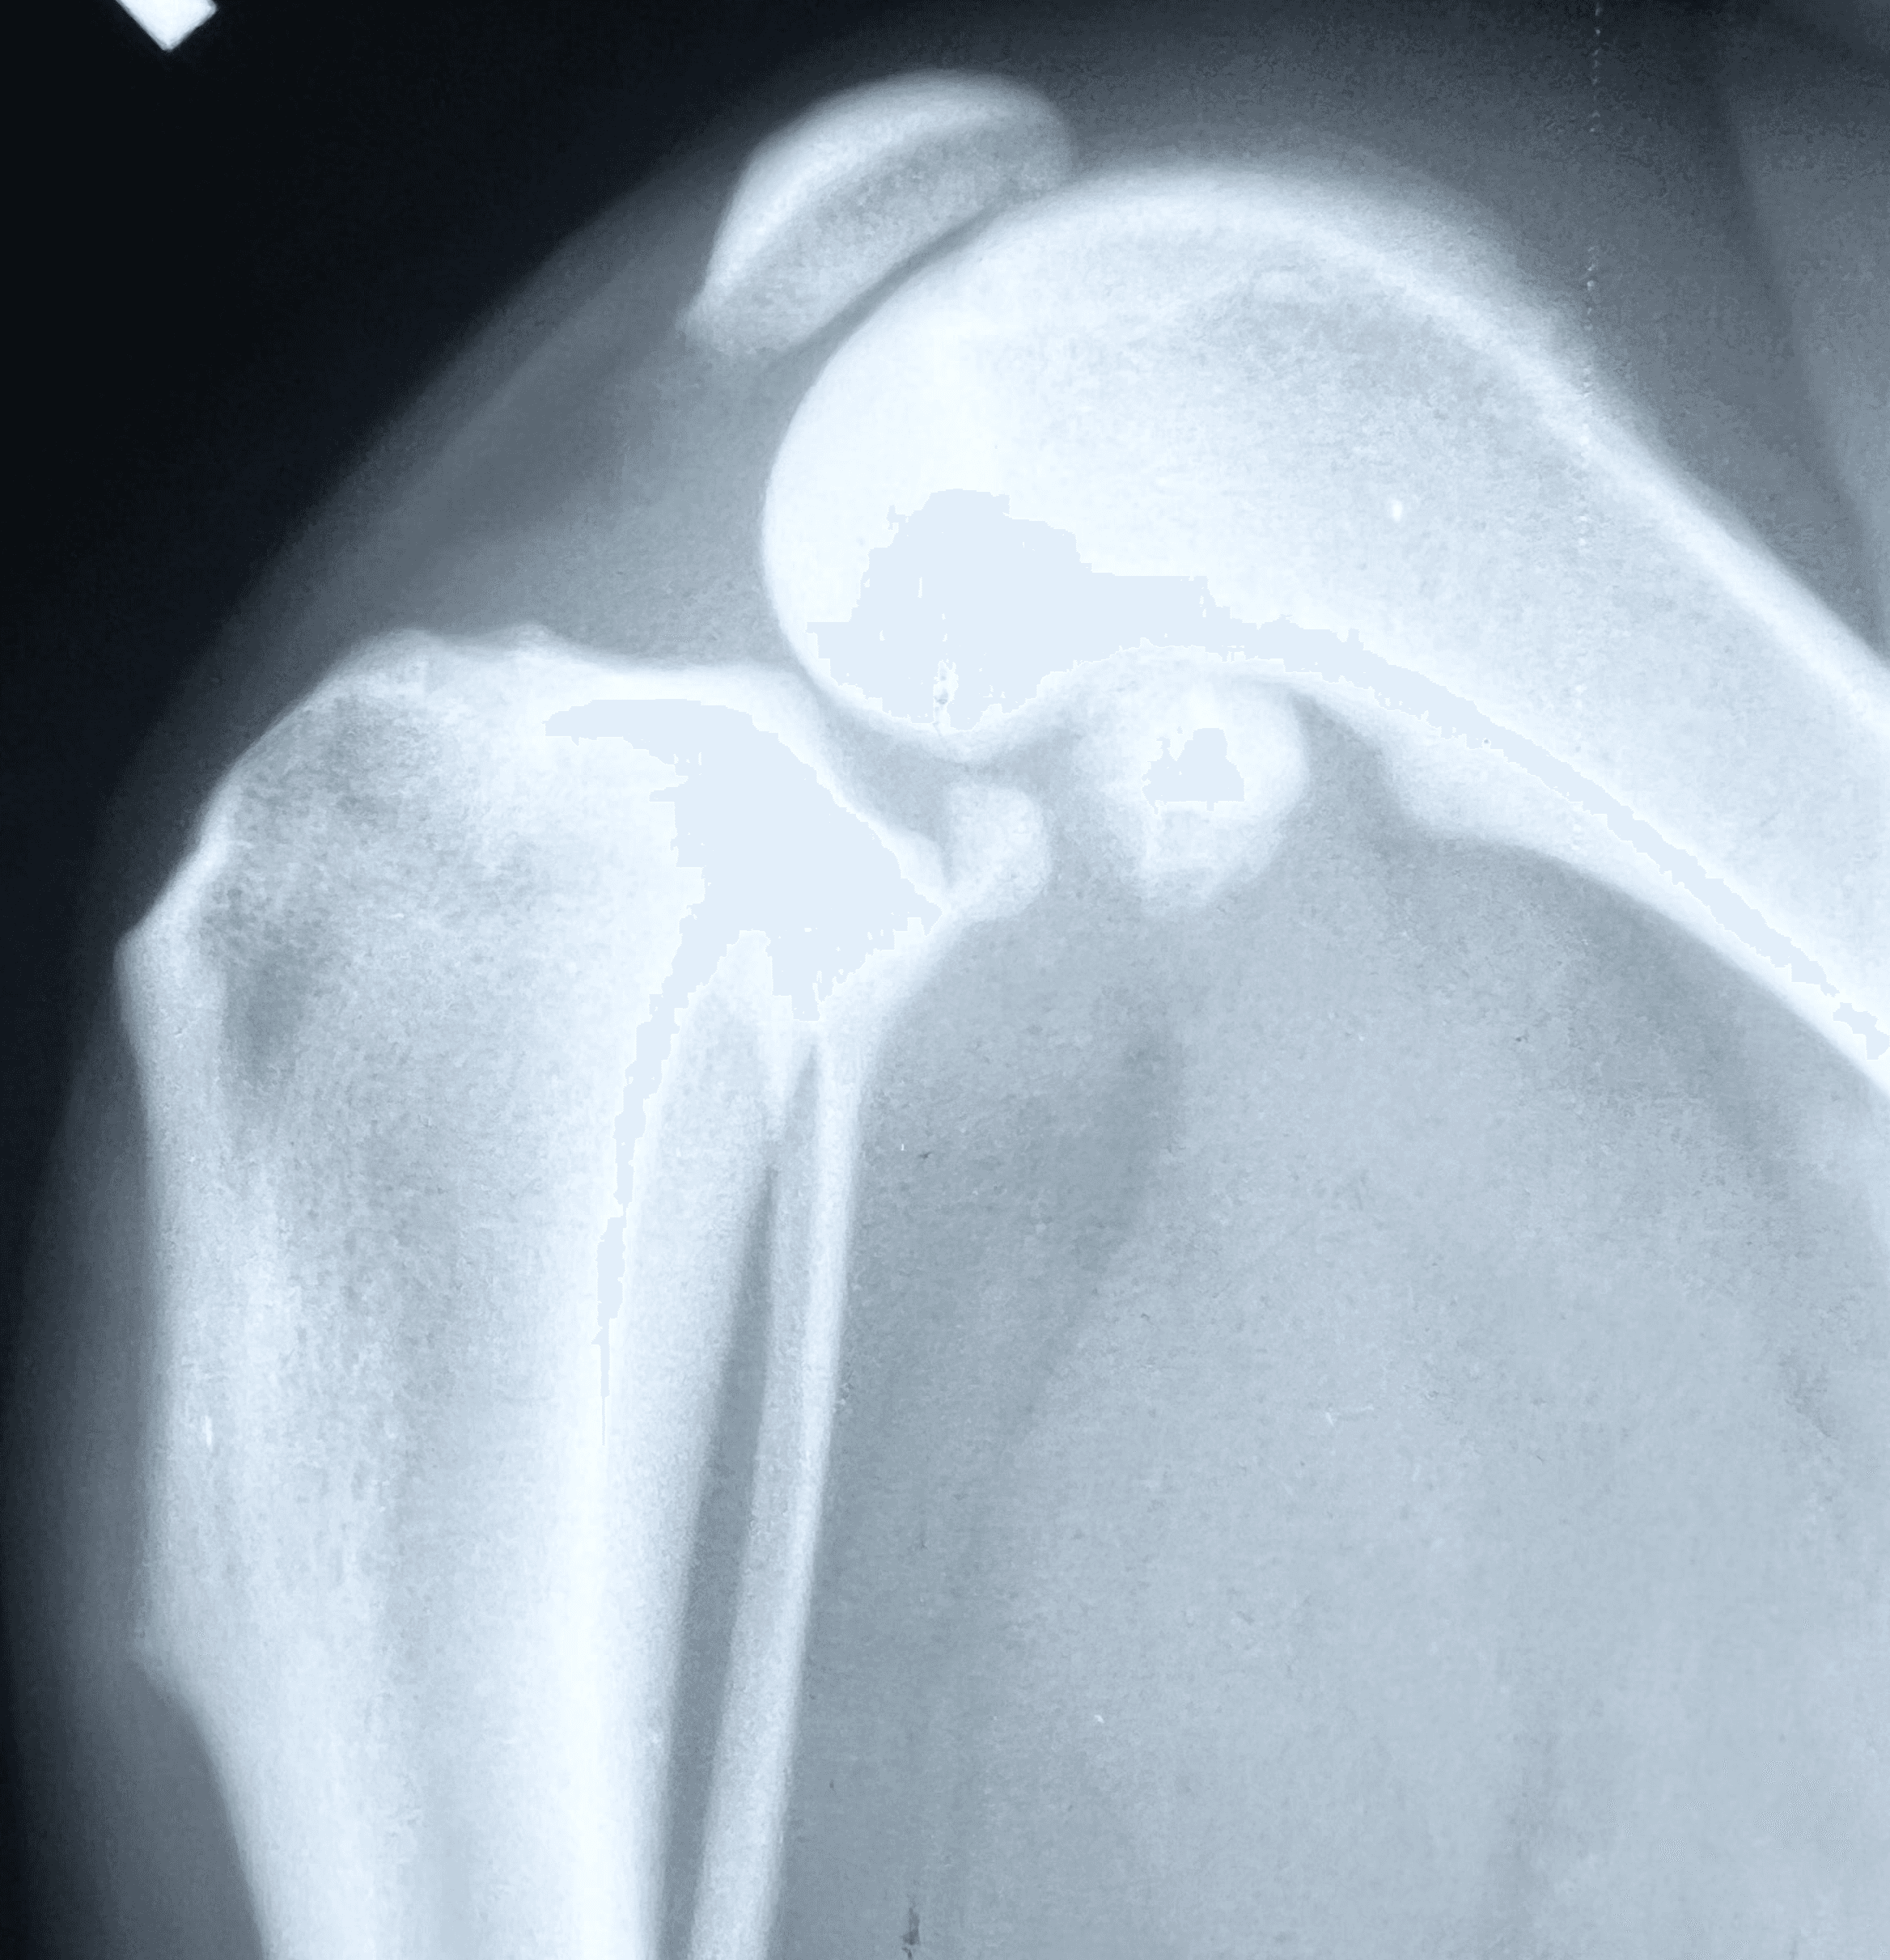

Diagnosis:

Diagnosis can be made from physical examination alone

but medical history and X-rays help to confirm the suspicion.

On exam, the veterinarian looks for abnormal forward movement of the tibia relative to the femur (known as cranial drawer or tibial thrust), which confirms damage to the ligament.

In partial tears, this motion may not be obvious, but pain on extension of the knee often helps identify the injury.